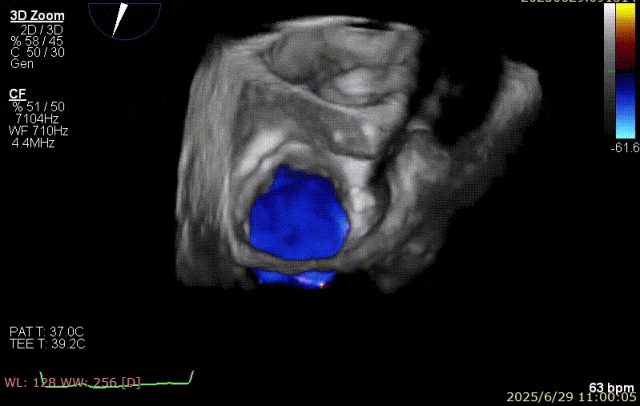

术前超声

患者术前 TEE 可见 P3 区脱垂二尖瓣环前后径(AP)约 37 mm,CC 径约 41 mm,瓣叶无明显钙化及裂隙,后瓣瓣尖探及一长约 9 mm 短带样回声漂附,二尖瓣口面积约 5.3 cm²。

经我院心脏超声检查提示:左房室增大伴二尖瓣后瓣脱垂(P3 区,腱索断裂)并重度关闭不全(Carpentier IIb 型,反流分级 4+);符合高血压性心脏病改变;少至中等量心包积液;左室舒张功能降低,收缩功能测定在正常范围并呈假性高排表现。